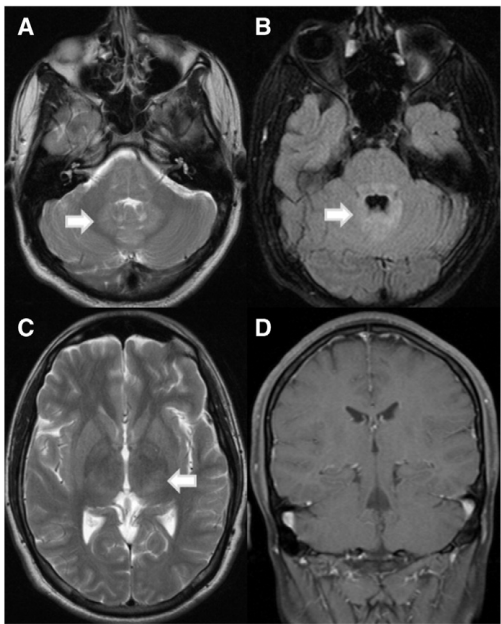

三天后,患者的病情恶化,对外部刺激反应差,瞳孔散大且对光线反应迟钝,任何肢体均无活动。不久后陷入昏迷,出现扩张而无反应的瞳孔、反射消失,并对疼痛刺激出现去大脑强直反应。入院后四天进行的脑部磁共振成像(MRI)扫描显示,在丘脑、脑桥和小脑的FLAIR和T2加权图像上有非增强的高信号(见图1)。腰椎穿刺结果如表1所示。在班加罗尔的国立心理健康与神经科学研究所神经病毒学部门的国家参考实验室,通过快速荧光灶抑制试验(RFFIT)检测到患者血清中的狂犬病病毒中和抗体滴度>1:16,000,脑脊液中的滴度>1:8000,这些结果是在病程的第34天获得的。随后对同一脑脊液样本进行了重复检测,结果呈阳性,滴度为1:130,000。由于后勤原因,未能对后续的脑脊液样本进行重复检测。

与狗或蝙蝠变种相关的人类狂犬病导致MRI异常,表现为脑干、丘脑、下丘脑、海马体和基底神经节、皮层下和深部白质以及脊髓前角的定义不明确的T2加权高信号:这些可能是由于病毒引起的神经元损伤所致[3,4,11,31,44,51](图1)。钆对比剂增强的病变(提示血脑屏障破坏)仅在狂犬病患者昏迷时出现,或在组织移植后感染的患者中出现[7,11]。